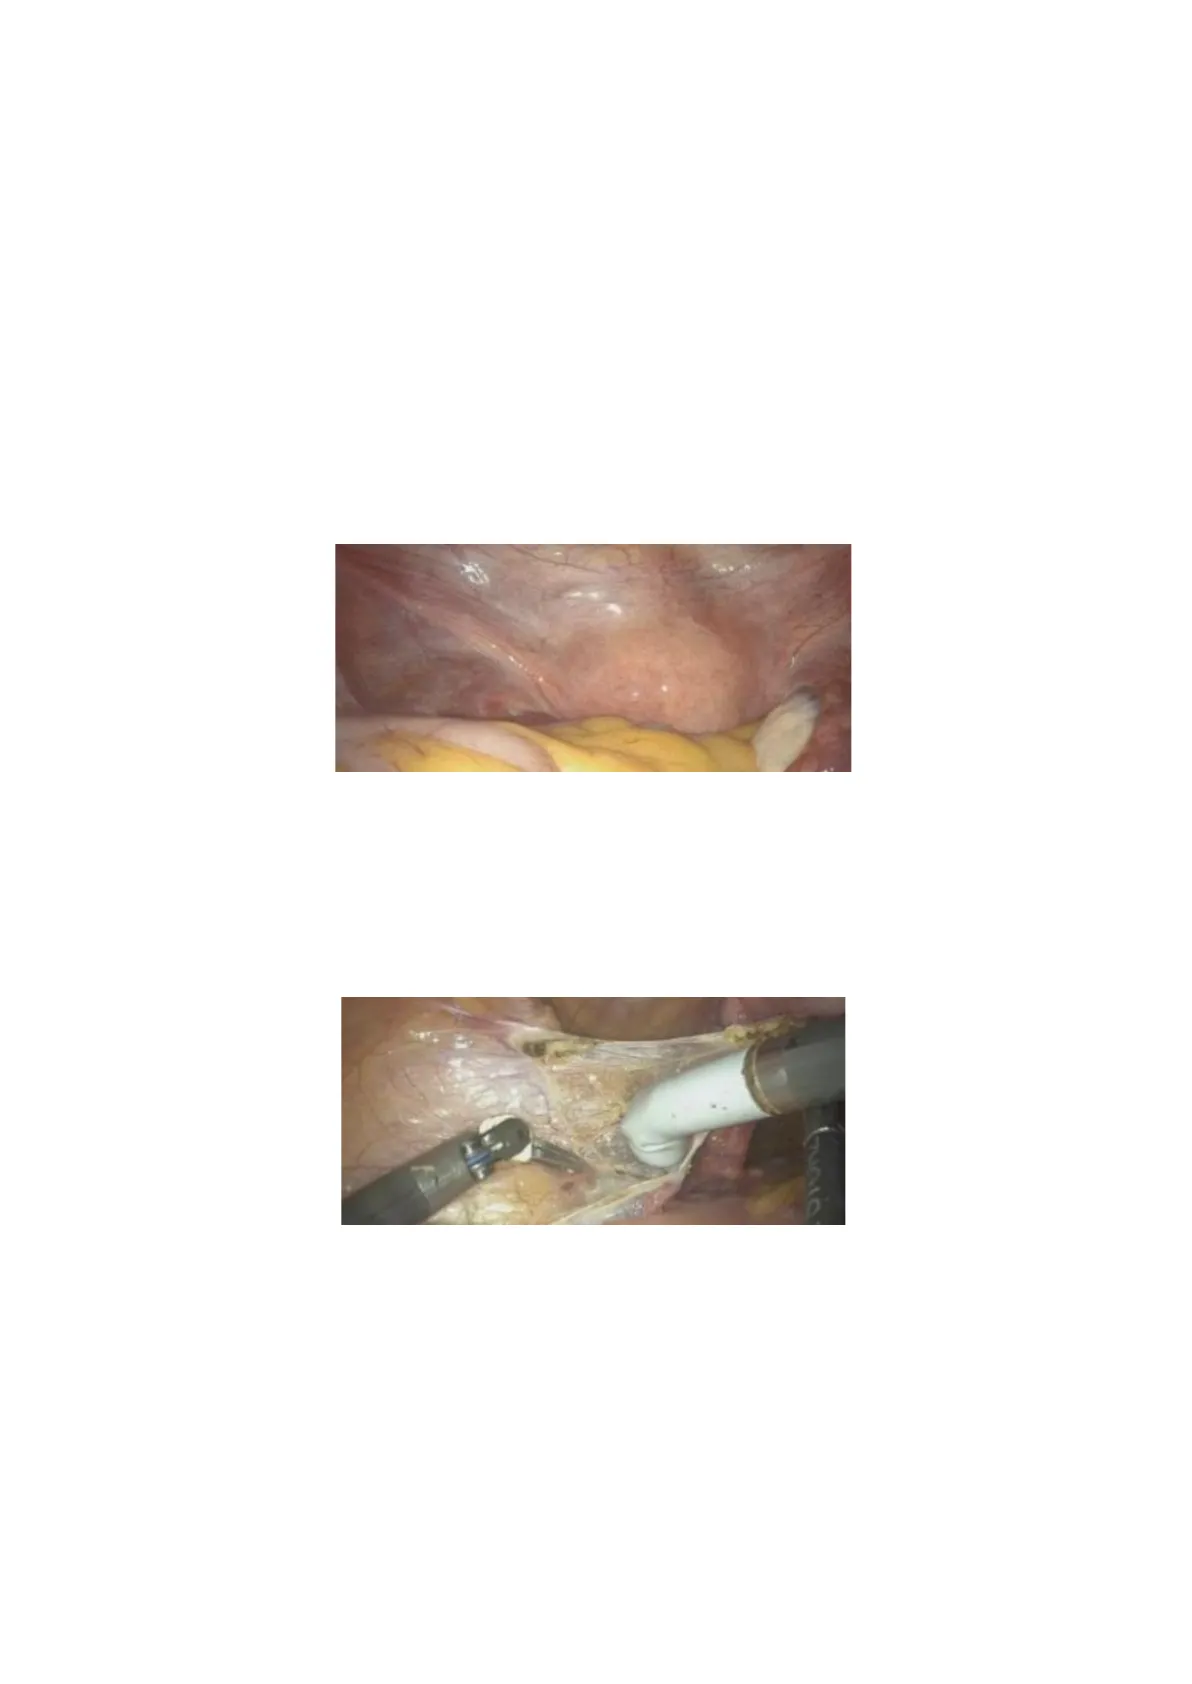

All the procedures we're discussing are performed using robotic surgery, and we use a uterine manipulator to help move the uterus during the operation. The first step is to cut the round ligament. Once it's cut, we gain access to the retroperitoneal space, where we can identify the key vascular structures that need to be either cut or preserved. Gunia One of the most important structures to identify is the ureter, that we must, of course, preserve. The next step is to locate, within the retroperitoneum, the vessels and the so-called "ureteric point," where we need to pay special attention. One crucial vessel to find is the umbilical artery.

As we mentioned, the uterine artery often branches off from the umbilical artery. While textbooks typically describe it as originating from the internal iliac artery, in practice, it often arises from the umbilical artery. Once we identify the umbilical artery, we can locate the ureter. If you remember, we said, "the water passes under the bridge." In this analogy, the "water" is the ureter, and the "bridge" is the uterine artery, which passes over it. Why is this important? If possible, we place a clip at the base of the uterine artery to stop the blood flow to theuterus, which helps reduce bleeding when we perform a total hysterectomy. We repeat the same steps on the opposite side.

The structure near the umbilical artery is the external iliac vessel. When performing a sentinel lymph node biopsy or lymphadenectomy, these vessels serve as important landmarks. After identifying all the structures, we create a window above the ureter to ensure we don't damage it when cutting the infundibulopelvic ligament.

That's the uterine artery. We place the clip here, where the uterine artery arrives. Therefore, there is minimal bleeding, especially because we close the artery at its base before proceeding. After cutting the arteries, the next step is to prepare both the anterior and posterior planes. Anteriorly, we need to identify and mobilize the bladder. This structure here is the bladder, and we must create enough space to perform the colpotomy without causing any injury.

To do this, we develop the vesico-uterine space by opening the peritoneum and carefully dissecting in this area. The incision is made through the peritoneum, and here you can see the bladder and the Foley catheter. Once this part is prepared, we identify the cervix and then the vagina.

In this case, we're using a uterine manipulator, which includes valves to help guide the incision. Alternatively, a sponge can be placed inside the vagina to maintain the pneumoperitoneum and guide the colpotomy. If we don't place anything in the vagina, we risk losing the pneumoperitoneum when the vaginal wall is opened. We are demonstrating a robotic hysterectomy, but the steps are the same for laparoscopic and open abdominal (laparotomic) approaches. Using robotic assistance just makes it easier to visualize and explain the procedure.After cutting the round ligament and entering the retroperitoneal space, we continue the dissection around the cervix.